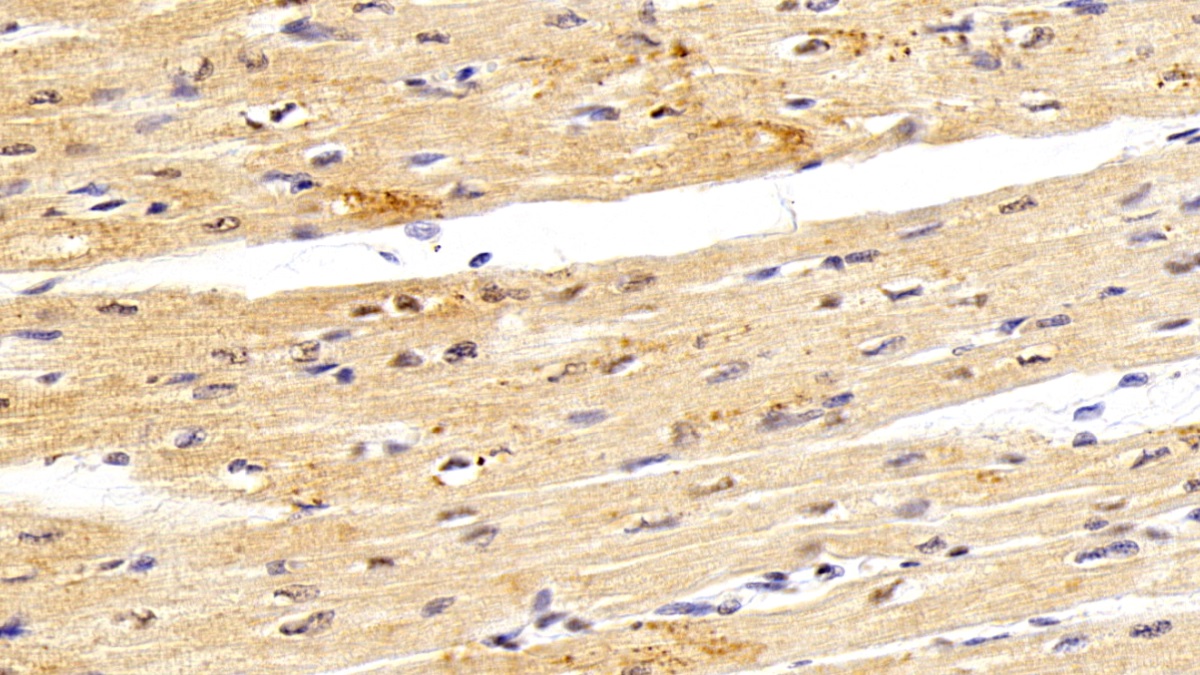

Использование высококачественных первичных антител является неотъемлемым условием получения точных и воспроизводимых результатов в современных научных исследованиях. Например, в рамках онкологического исследования удалось достоверно идентифицировать экспрессию белка PD-L1, что сыграло ключевую роль в оценке потенциальной эффективности иммунотерапии. Применение надежных антител обеспечило стабильность сигнала и высокую специфичность детекции, что позволило получить данные, пригодные для публикации в рецензируемых научных изданиях.

Способы применения первичных антител

Первичные антитела используют в разных методах: от вестерн-блоттинга до иммунофлюоресценции и проточной цитометрии. Всё решает подготовка: нужно грамотно выбрать буфер, точно рассчитать, сколько продукта добавить, и не затянуть с инкубацией. Например, в вестерн-блоттинге без правильной блокировки мембраны фон может всё испортить, а в иммунофлюоресценции фиксация клеток решает, будет ли сигнал ярким. Мы не просто продаём реагенты, а помогаем довести эксперимент до результата: подбираем реагенты и даём советы по методам, если есть специфика в протоколах производителя. Нужен особый подход? Оформите спецзаказ по ссылке — мы найдём решение для вашего проекта.